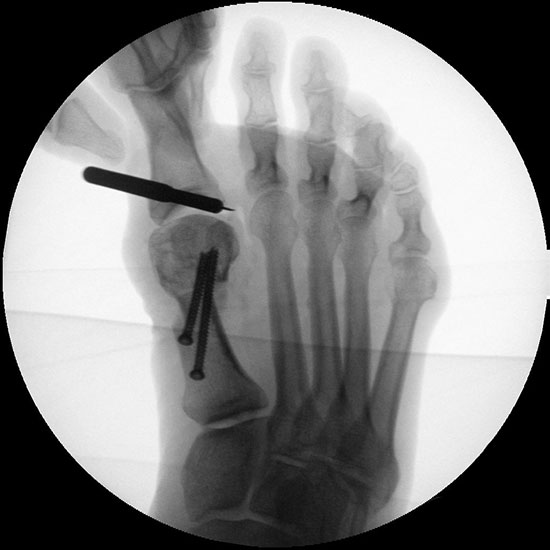

Abbildung 1

• Korrekturpotential größer als beim offenen Chevron, da die Gelenkkapsel als stabilisierendes Element erhalten bleibt und über eine trikortikale Osteosynthese mit zwei kanülierten Schrauben eine Verschiebung bis ca. 80% des Metatarsaledurchmessers möglich ist (Abb. 1).